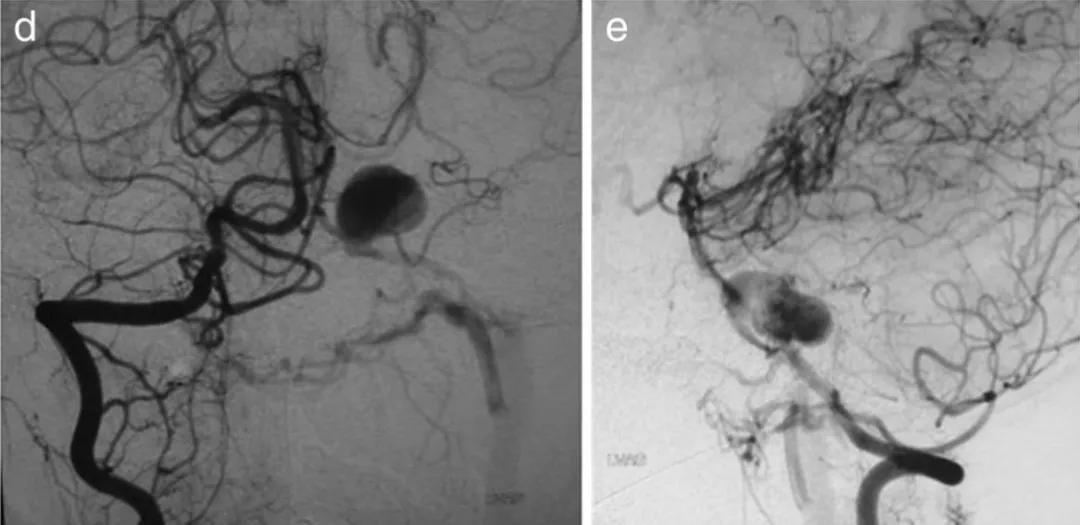

图a、b、c显示第7天右椎动脉造影,可见动脉瘤位于左小脑前下动脉近端

第14天复查造影显示动脉瘤明显增大,破裂风险显著增加

图d、e显示第14天右椎动脉造影,动脉瘤扩大,动静脉瘘更加明显